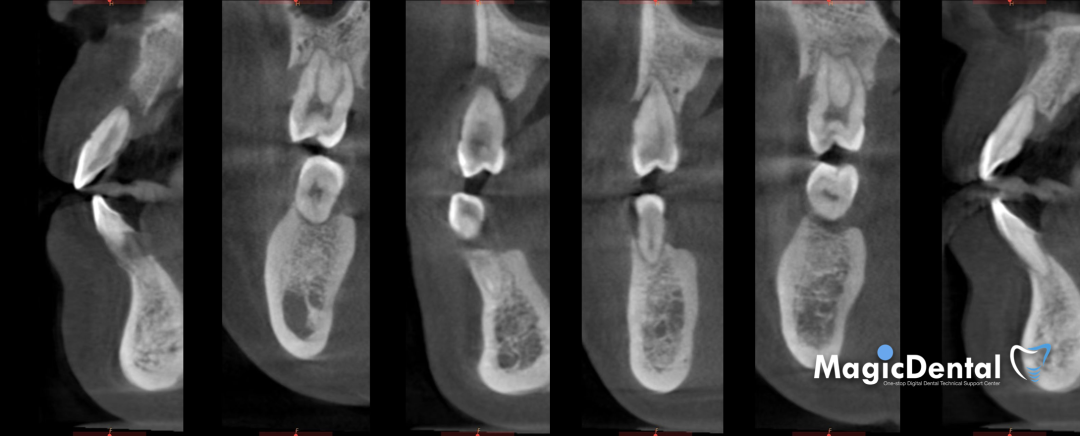

CT显示牙槽骨水平吸收严重,大多数吸收至根尖。

术前CBCT

CBCT显示全口牙槽骨水平吸收严重,下颌骨量保存大于上颌

术后三个月复查CBCT